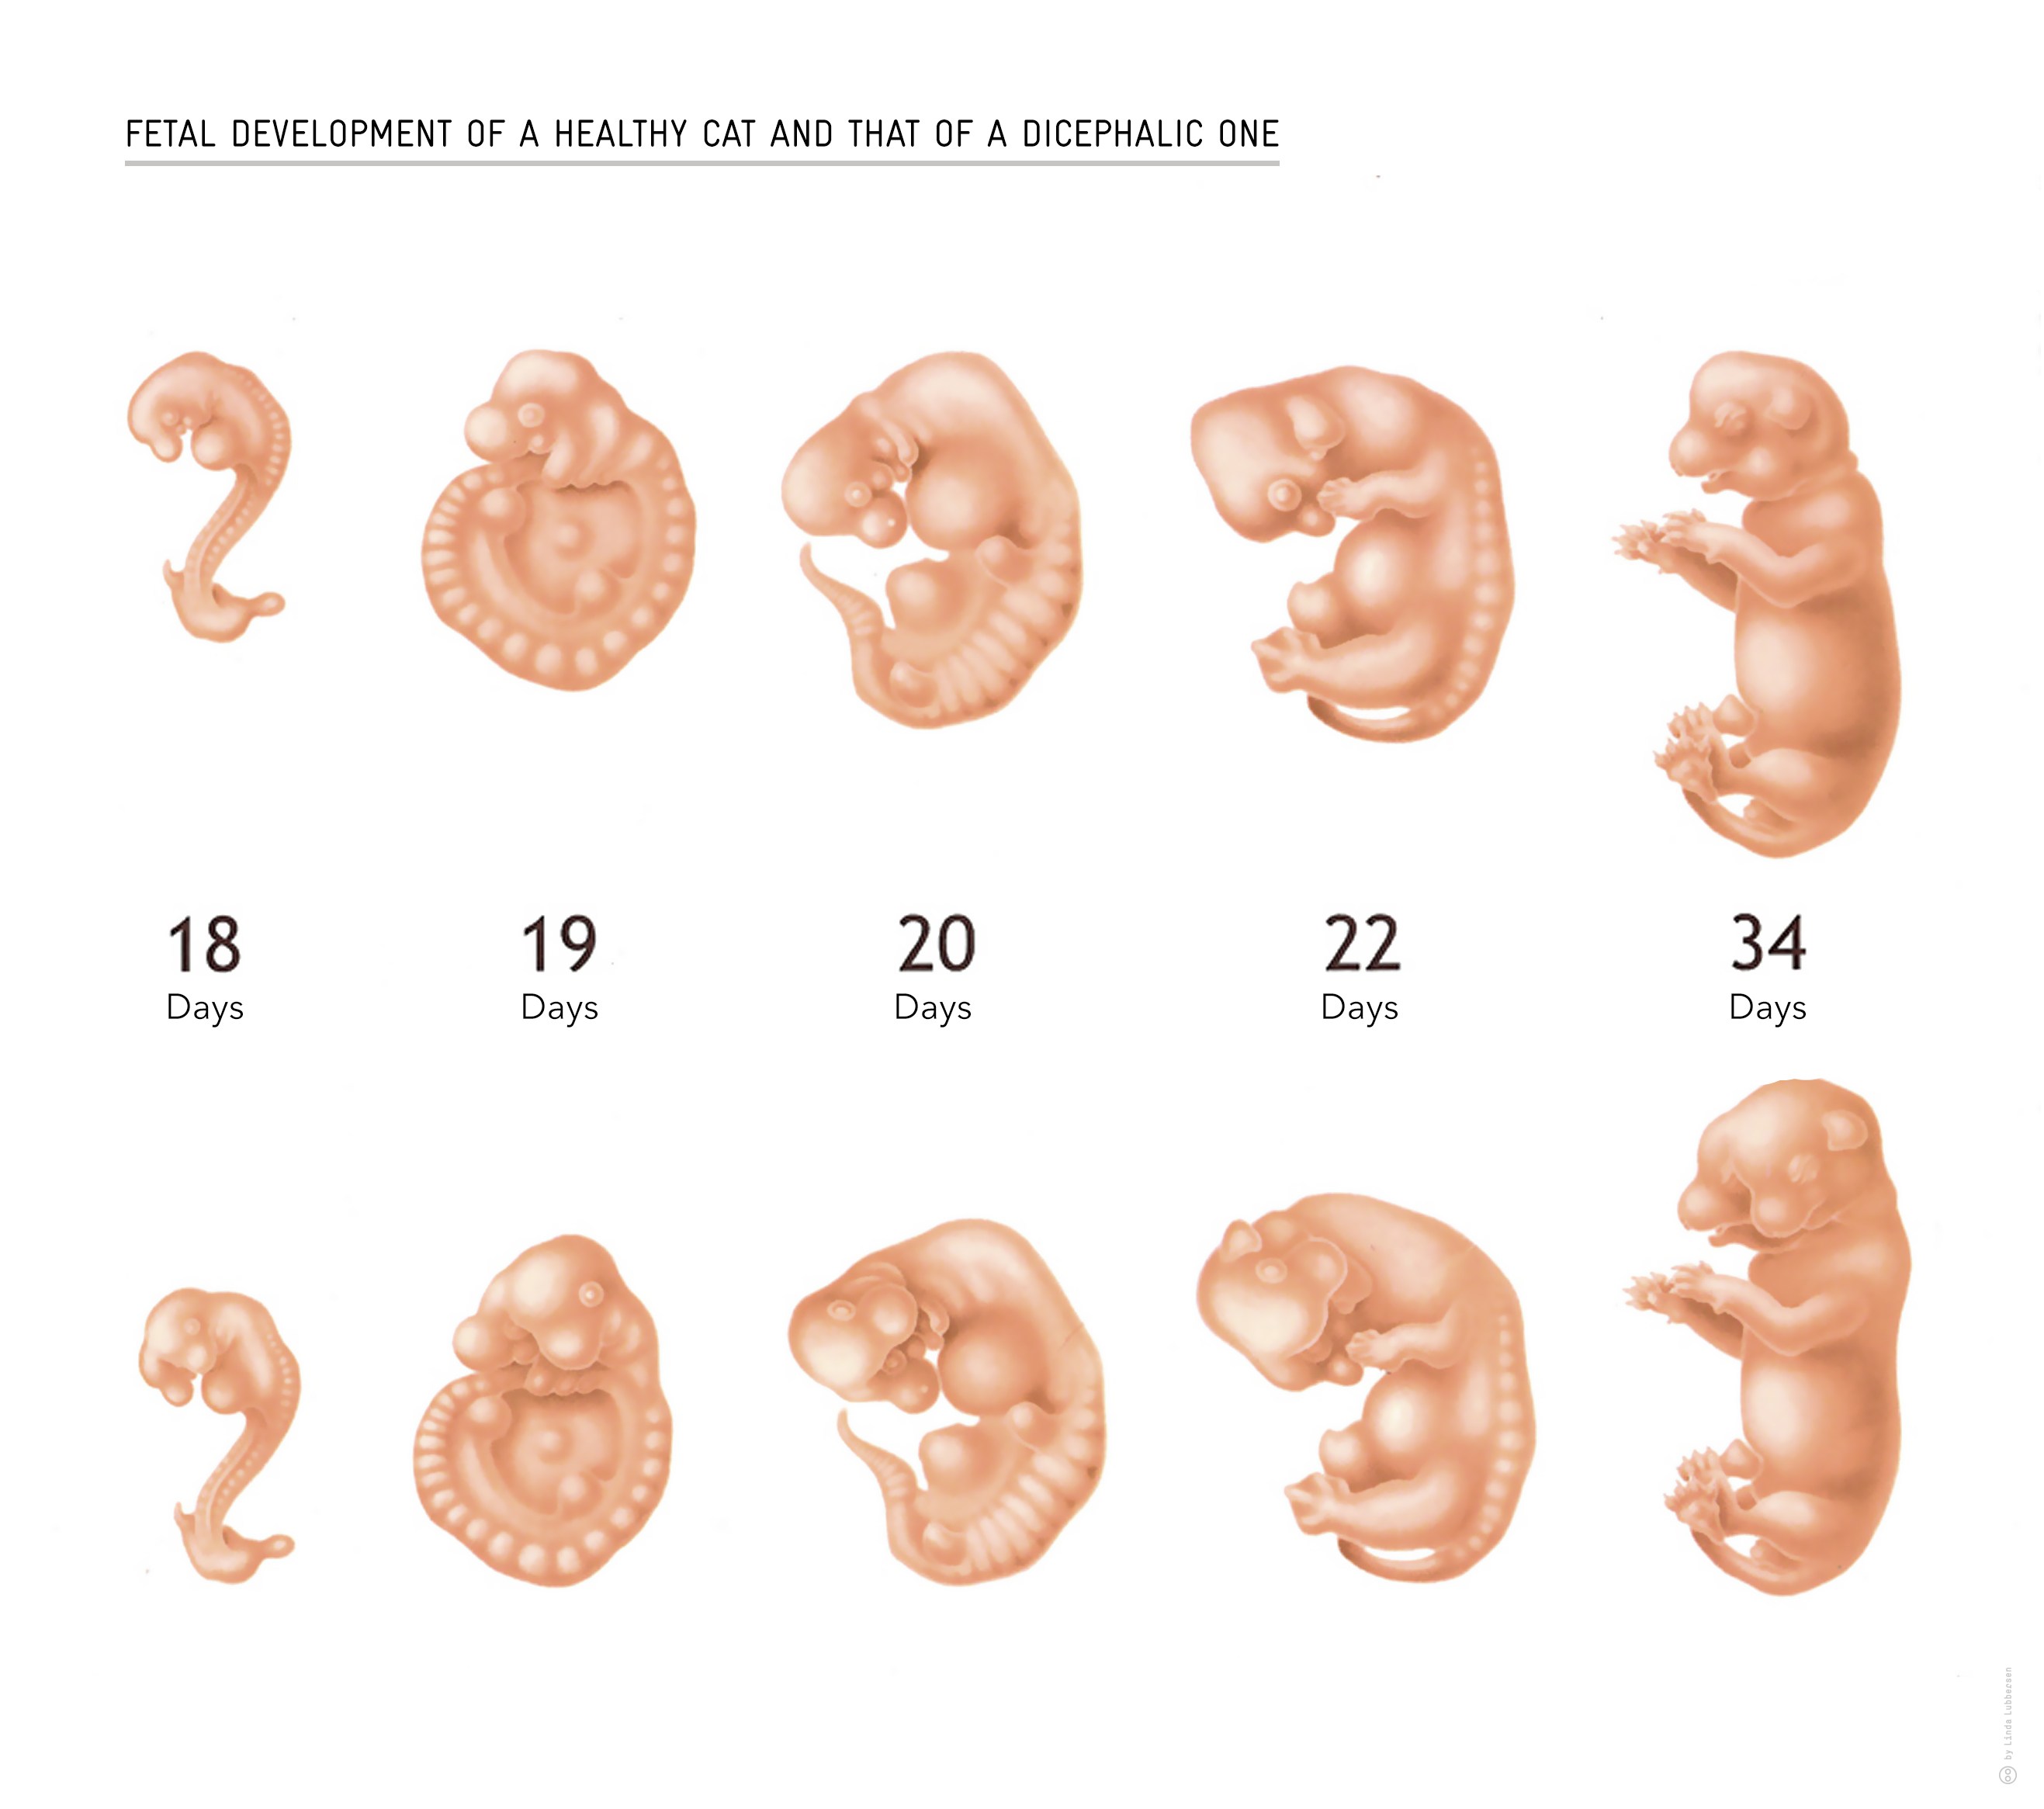

Фотография Плода В Животе

Фотография Плода В Животе 113 фотографий